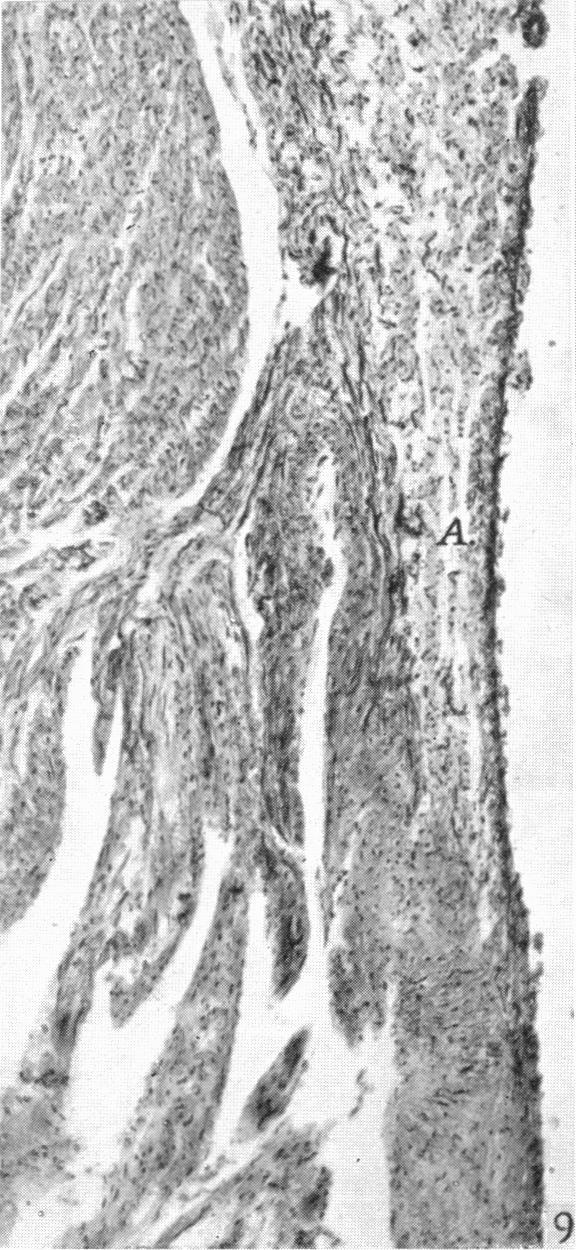

The development of the atrio-ventricular valves in man.

J Anat. 1939 Jul;73(Pt 4):643-57.